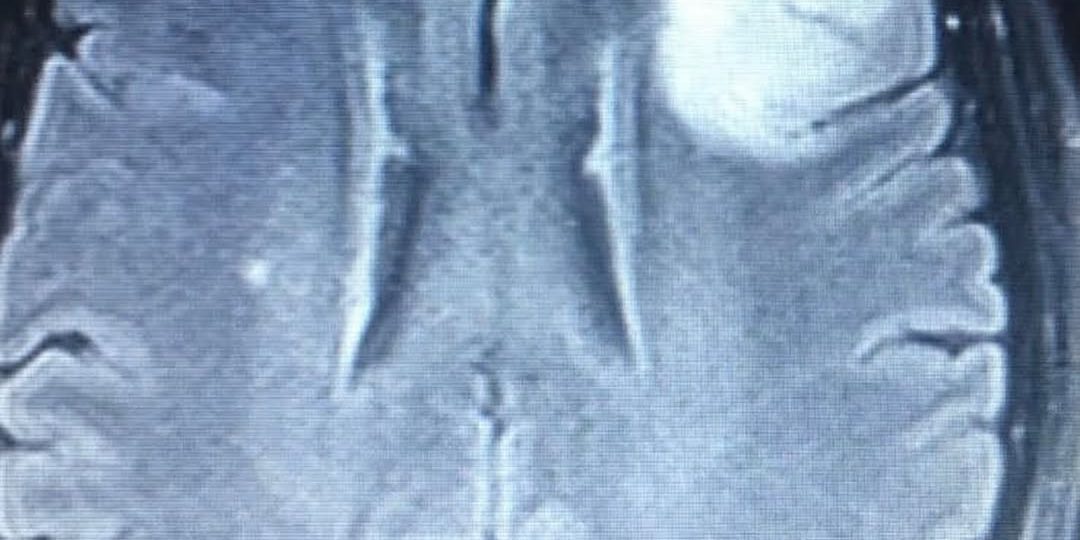

Local anesthesia is one of the oldest forms of anesthesia and is adequate for opening the skull to remove a tumor. A patient with a tumor in the left frontal or temporal region such as this young lady that I operated upon recently can be monitored for their speech function while the tumor is removed under local anesthesia.